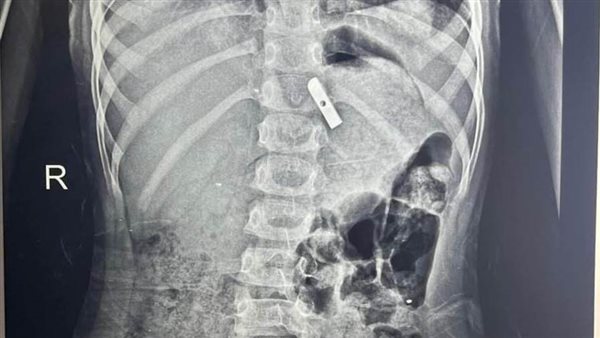

وتم حجز الطفلة فورًا بالمستشفى، وإجراء الفحوصات اللازمة من أشعة وتحاليل، التي كشفت عن وجود جسم غريب داخل المعدة.

وعلى الفور أدخلت الطفلة إلى غرفة العمليات، حيث تم استخراج قطعة معدنية حادة من براية قلم رصاص كانت مغروسة في جدار المعدة، باستخدام منظار الجهاز الهضمي.